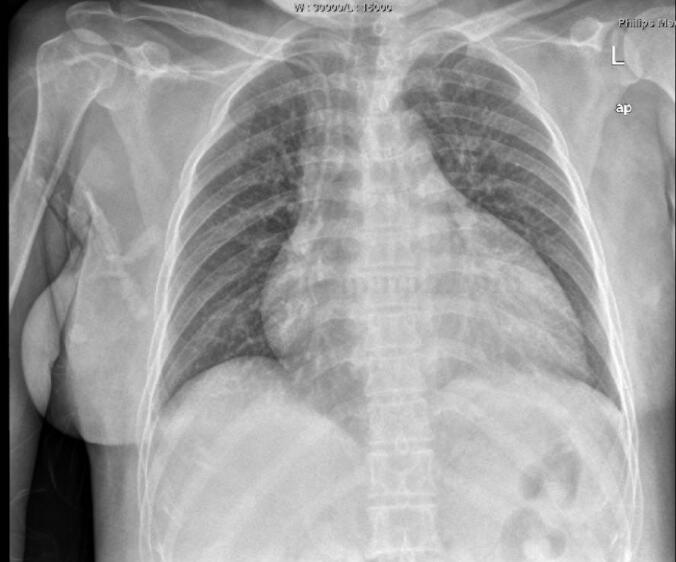

急诊生化:ALT710.7U/L,AST2585.7U/L;U REA4.9mmol/L,CREA97μmol/L,UA337μmol/L,K+3﹒54mmol/L。尿常规隐血+++。便常规无异常。血常规:WBC16.57×199/L,N89.9%。BNP>9000pg/ml,尿渗透压222mOsm/(kg•H2O)。凝血:D‐二聚体6593ng/ml,APTT58.9秒,PT 38﹒7秒。甲状腺功能:FT31﹒03pg/ml,T43﹒36μg/dl,FT40﹒388ng/dl,T30﹒408nmol/L,TSH0.12μIU/ml。血清泌乳素测定0.22ng/ml,血清促卵泡刺激素测定1.00IU/L,雌二醇测定15pg/ml,睾酮测定0.01ng/ml,孕酮测定0.15ng/ml,血清促黄体生成素测定0.19MIU/ml。皮质醇节律(0点、8点、16点):1002nmol/L、413.4nmol/L、1391nmol/L;ACTH(0点、8点、16点):74.1pg/ml、41.6pg/ml、47.2pg/ml。心电图检查见图1。心脏彩超:LVDd60mm,EF 46%,左心房、左心室增大,心包积液(少量)。胸片(2011‐7‐3)检查见图2。

图2 双肺纹理增多,心影增大

入院后于ICU予重症监护,抗感染、激素替代、多巴胺及多巴酚丁胺强心、升压以及维持水、电解质、酸碱平衡等对症支持治疗,以及气管插管呼吸机辅助通气、营养支持治疗。于6月30日患者出现2次室颤,经除颤、激素替代、纠正电解质紊乱等治疗均抢救成功。患者自主呼吸逐步恢复。于7月3日拔除气管插管。多次查脑钠肽>9000pg/ml。胸片提示心影明显增大。患者有甲状腺功能减退,但考虑患者急性心力衰竭很严重,ICU医师因担心补充甲状腺素后引起心功能恶化,转入CCU继续治疗。根据甲状腺功能调整糖皮质激素以及甲状腺素片用量,根据血压情况调整降压用药,因此类患者易发生栓塞事件,予低分子肝素抗凝治疗。患者病情逐步稳定。2011‐9‐13复查心脏彩超:LAD40mm,LVDd50mm,EF 55%。左心房、左心室稍大;左心室舒张功能减退。出院后2011年11月复查胸片见图3。

患者的心力衰竭为长期甲状腺功能减退引起甲状腺功能减退性心脏病所致。感染诱发心力衰竭急性发作。甲状腺功能减退性心脏病是由于甲状腺素合成、分泌不足或生物效应不足而引起心肌收缩力减弱,心排血量和外周血流量减少等引发的一系列症状和体征的内分泌紊乱性心脏病。因甲状腺本身疾病引起的功能减退称原发性甲状腺功能减退或甲状腺性甲状腺功能减退,占甲状腺功能减退的90%~95%。缘于垂体及下丘脑病变的甲状腺功能减退系中枢性甲状腺功能减退或继发性与三发性甲状腺功能减退。该患者属席汉综合征继发性甲状腺功能减退。治疗主要是控制急性心力衰竭的同时补充糖皮质激素及甲状腺激素。甲状腺功能减退所致心脏扩大,治疗主要以补充甲状腺素为主,随着甲状腺功能逐渐恢复,心脏也会逐渐回缩,该患者出院后仍坚持服用甲状腺激素,心功能保持良好,复查胸片心影已恢复正常大小。